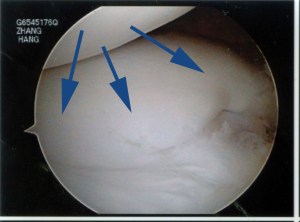

This is my patient who is 18-years-old and she presented with acute locking and pain in the right knee. MRI confirmed a torn discoid lateral meniscus.

Arthroscopy was performed.

The discoid lateral meniscus was torn and detached from the capsule and has buckled into the inside of the joint. It looked like this: